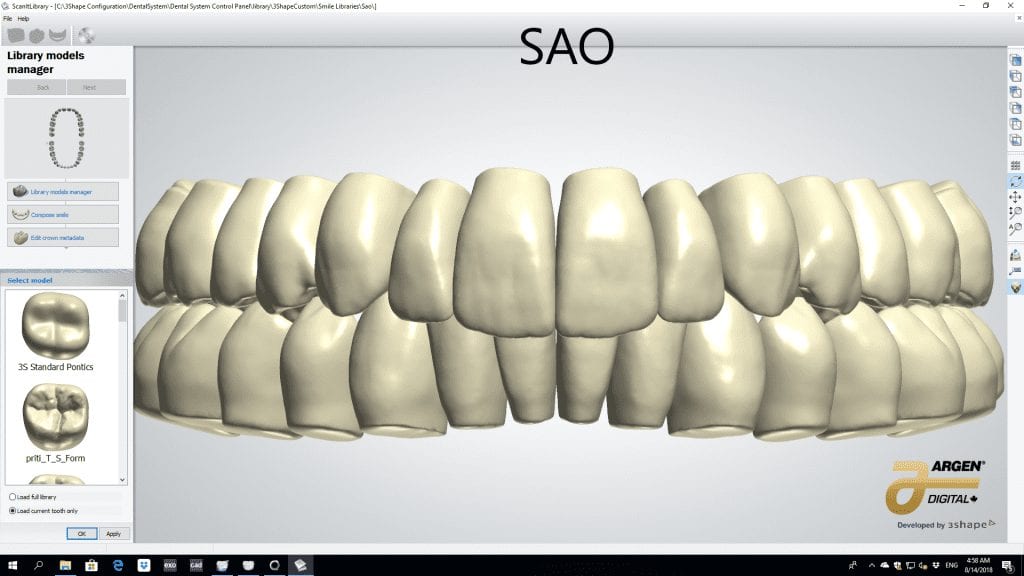

The digital models were then imported into a third party software where a library of tooth morphologies are available for the clinician to choose from.

Once the appropriate library is chosen, the digital wax ups are performed. In the subsequent photos you can see the transparent overlay of the wax-ups to the original position of the existing dentition